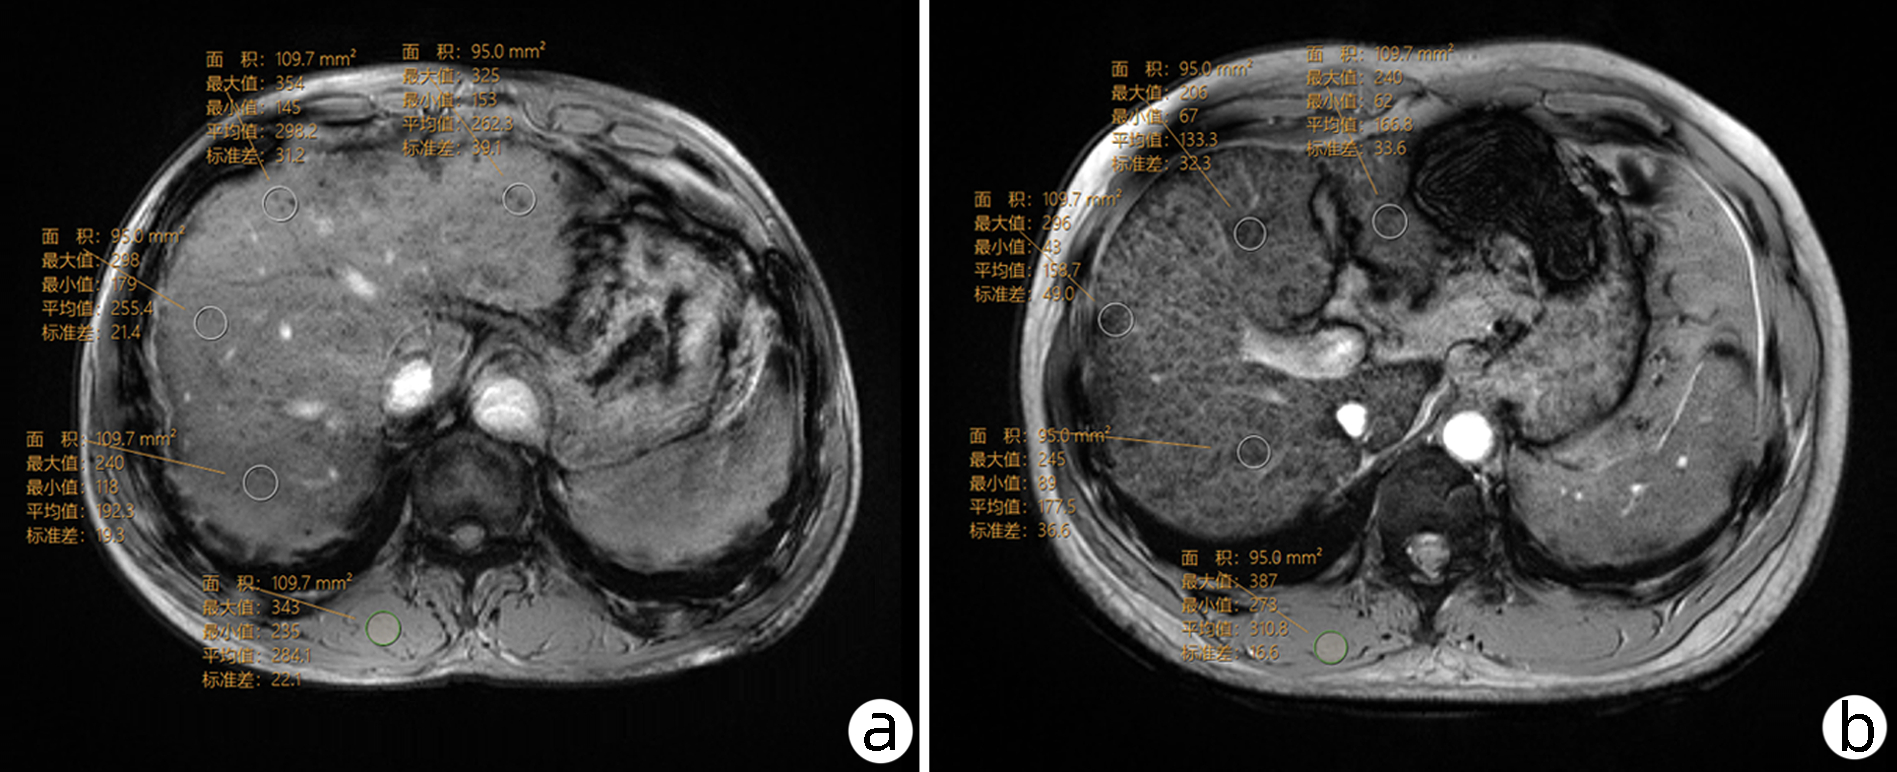

肝肌信号强度比及血清标志物对慢性乙型肝炎肝纤维化的诊断价值

温雅, 屈兆宇, 鲁景楠, 阴玮灵, 黄晓旗

2023, 39(3): 573-579. DOI: 10.3969/j.issn.1001-5256.2023.03.014

摘要(903) HTML (277) PDF (2480KB)(111)

摘要:

目的  结合ALT和肝脏硬度值水平分组,探讨磁敏感加权成像(SWI)的肝肌信号强度比(LMR)及血清标志物诊断慢性乙型肝炎纤维化严重程度的价值。  方法  回顾性收集2018年10月—2021年9月就诊于延安大学附属医院的慢性乙型肝炎患者255例,将患者分为严重肝纤维化(SLF)组77例与非SLF组178例,SLF组定义为ALT水平在正常范围内且肝脏硬度大于9.0 kPa,或ALT水平高于正常值上限1~5倍且肝脏硬度大于12.0 kPa的患者。在SWI序列下测量肝脏的平均SWI值(SWIliver)及竖脊肌信号强度并计算LMR。正态分布的计量资料2组间比较采用t检验,非正态分布的计量资料2组间比较采用Mann-Whitney U检验。计数资料组间比较采用χ2检验。利用二元Logistic回归分析SLF的影响因素。采用受试者工作特征(ROC)曲线分析LMR及其联合血清学的诊断效能,使用DeLong检验比较不同AUC的差异。  结果  SLF组较非SLF组的ALT(Z=-3.569, P<0.001)、AST(Z=-5.495, P<0.001)、透明质酸(HA)(Z=-6.746, P<0.001)、层粘连蛋白(LN)(Z=-5.459, P<0.001)、Ⅳ型胶原(Ⅳ-C)(Z=-8.470, P<0.001)、Ⅲ型前胶原(PCⅢ)(Z=-6.326, P<0.001)、APRI(Z=-9.004, P<0.001)、FIB-4(Z=-8.357, P<0.001) 高,较非SLF组的PTA(t=10.088, P<0.001)、PLT(t=9.163, P<0.001)、SWIliver(t=2.347, P=0.02)、LMR× 10(Z=-4.447, P<0.001)低。PTA、HA、Ⅳ-C、LMR×10为发生SLF的独立影响因素(P值均<0.05)。LMR×10诊断SLF的ROC曲线下面积(AUC)为0.675(95%CI: 0.614~0.732), 高于SWIliver的0.594(95%CI: 0.531~0.655)(Z=3.984, P<0.001),PTA+HA+Ⅳ-C+LMR×10(AUC=0.937, 95%CI: 0.896~0.966)的诊断效能优于PTA+HA+Ⅳ-C(AUC=0.905, 95%CI: 0.858~0.941)(Z=2.228, P=0.026)。  结论  LMR及血清标志物可较准确区分SLF,LMR为一项定量、客观的影像学指标,优于SWIliver,并可提升血清学标志物对临床判定SLF的诊断效能。